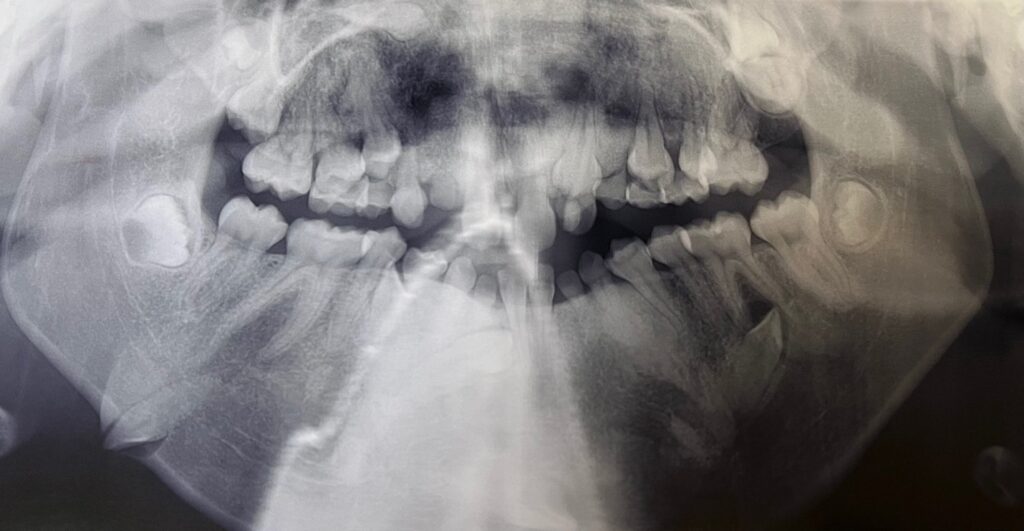

17-year-old girl with anterior mandible lesion

A 17-year-old girl was referred to the oral surgeon’s office by an orthodontist due to a lesion noted on a panoramic film at the anterior man…